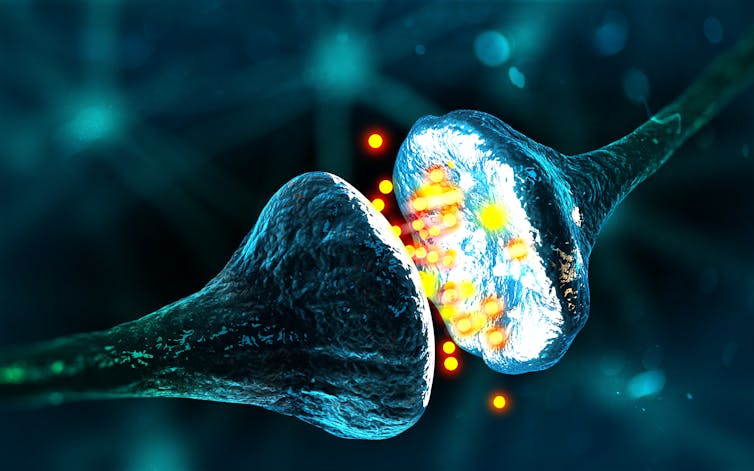

Even short-term exposure to toxic beta-amyloid can also reduce the ability of the brain cells’ synapses to be able to change how they communicate and create connections with other cells (an ability brain cells have, known as synaptic plasticity). Synaptic plasticity plays an important role in our ability to learn and remember.

Previous animal studies have found that oxytocin can strengthen social memory and improve spatial memory during motherhood in mice. But, until now, no studies had investigated whether oxytocin could stop toxic beta-amyloid from lowering synaptic plasticity – potentially with beneficial effects for memory in Alzheimer’s disease.

Using brain samples from male mice, researchers treated them with toxic beta-amyloid. This was to confirm that the protein does indeed cause the brain’s synaptic plasticity to worsen. Then they treated samples with toxic beta-amyloid and oxytocin together. This seemed to stop the toxic beta-amyloid from negatively affecting synaptic plasticity. But when the samples were treated with oxytocin on its own, they found it had no effect on improving synaptic plasticity.